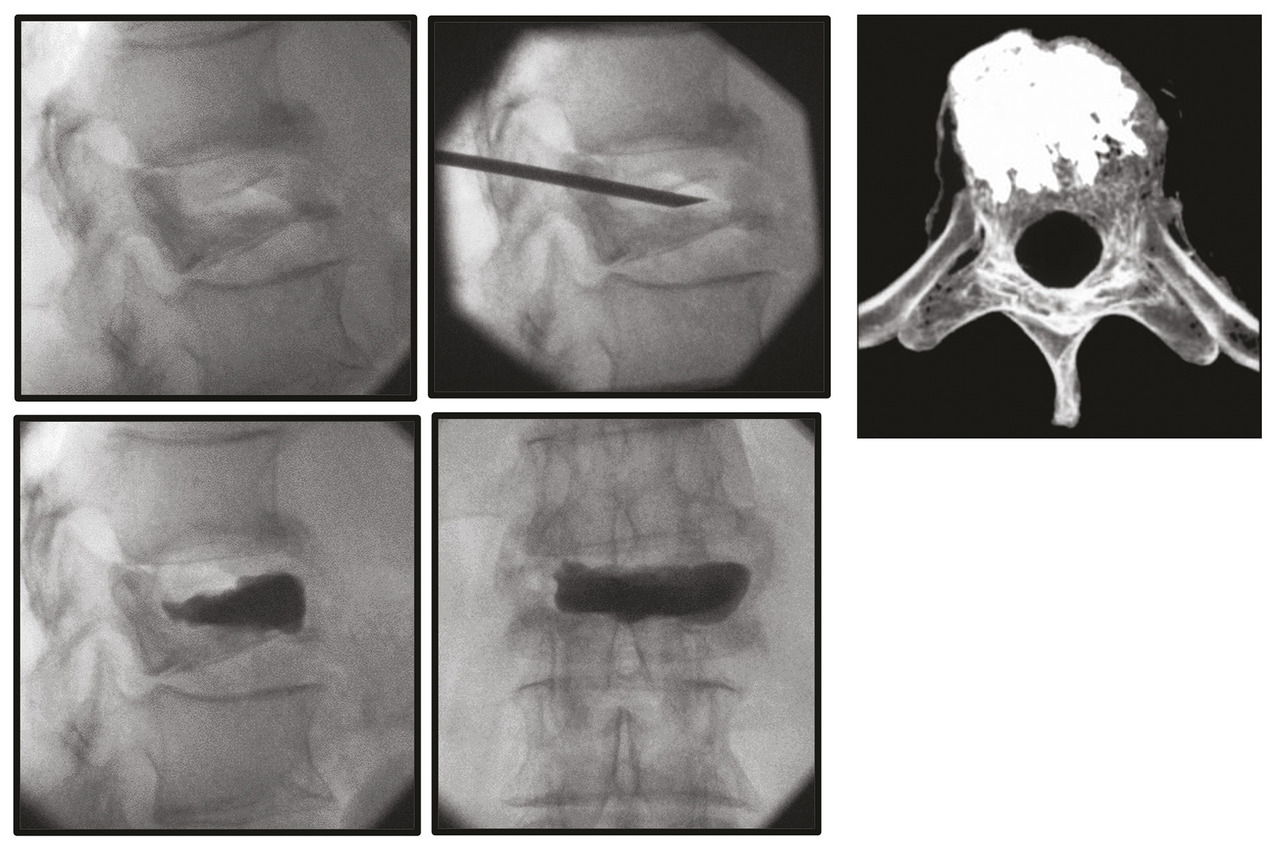

L’arthrose n’est pas seulement responsable d’ostéophytes rétrécissant le canal, elle s’accompagne aussi d’usure articulaire. Le rachis est alors déstabilisé. Le mouvement anormal est responsable de douleurs rachidiennes. Le déplacement engendré peut aboutir à une sténose fixée ou dynamique (spondylolisthésis dégénératif) limitant le périmètre de marche. L’usure du disque et des articulaires décoapte les vertèbres qui se déplacent l’une par rapport à l’autre. Cette déformation se fait le plus souvent vers l’avant (déséquilibre antérieur) mais aussi en rotation pour donner lieu à une scoliose dégénérative de novo ou accentuer une scoliose existante.

L’ostéosynthèse moderne permet de fixer solidement le rachis. Les vis pédiculaires,5 au besoin aidées par le cimentage du corps vertébral, sont utilisées couramment dans tous les services de chirurgie du rachis. L’immobilité obtenue est le meilleur moyen de lutter contre la douleur.6 Mais l’ostéosynthèse permet aussi la réduction de la déformation dans les trois plans de l’espace (fig. 3 et 4 ). L’équilibre rachidien restitué facilite la reprise de la marche et redonne une vie plus facile au patient qui a subi dans son dos le poids des ans.7 L’ostéosynthèse est solide et permet un lever immédiat en règle générale sans contention externe. Une greffe osseuse pérennise le montage le protégeant d’un démontage ou d’une fracture du matériel.

L’ostéosynthèse moderne permet de fixer solidement le rachis. Les vis pédiculaires,5 au besoin aidées par le cimentage du corps vertébral, sont utilisées couramment dans tous les services de chirurgie du rachis. L’immobilité obtenue est le meilleur moyen de lutter contre la douleur.6 Mais l’ostéosynthèse permet aussi la réduction de la déformation dans les trois plans de l’espace (